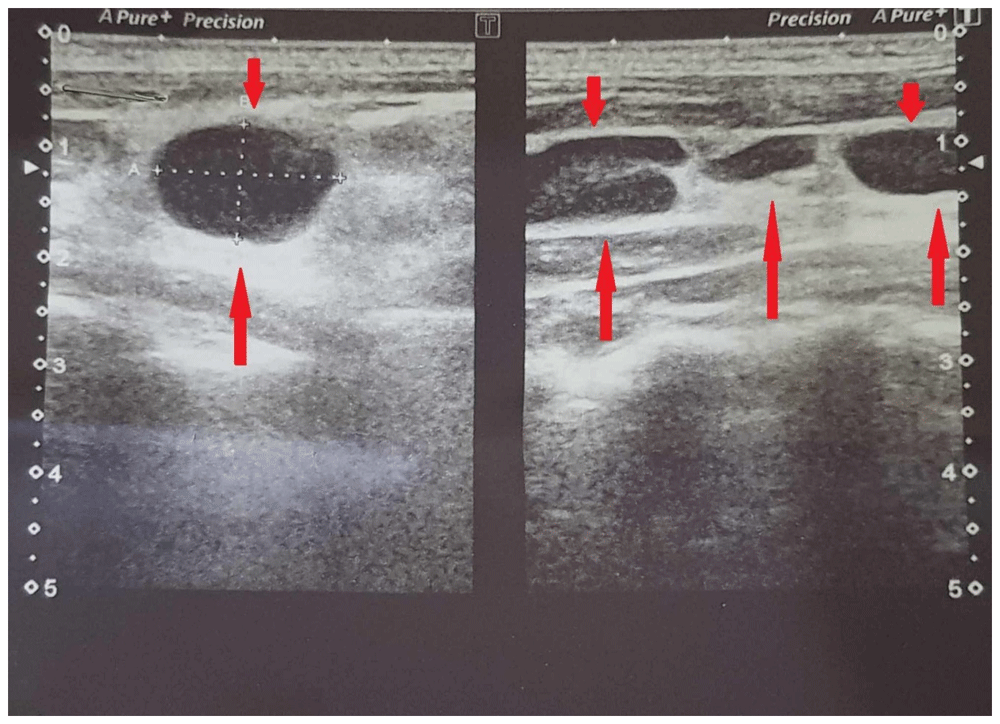

A provisional diagnosis of tuberculous lymphadenitis was made based on his occupation. Further investigations were ordered to determine the size and extent of the lymphadenopathy. These included ultrasonography of the neck and abdomen, to visualize any hidden lymphadenopathy that might have been missed during the initial physical examination; chest x-ray, to rule out any active tuberculosis; and interferon-gamma release assay.

On ultrasonography (Figure 1), the patient showed enlarged multiple discrete left cervical and supraclavicular lymph nodes measuring up to 16×10mm. The rest of the ultrasound report did not show any abnormalities. Chest x-ray was normal and interferon-gamma release assay was not conclusive.